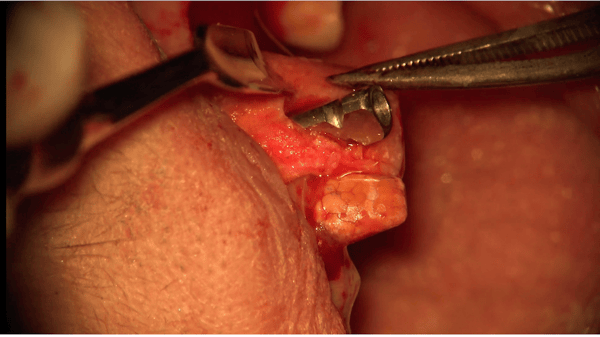

The OsteoGen Bone Grafting Strip infuses bone graft into a collagen strip to eliminate the problems associated with particulate migration. Unlike the Osteogen Plugs, which are generally used when all the socket walls are intact, the Osteogen Strips are perfect to repair a missing wall or defect.

- Use around immediate implant placement to fill gaps between the implant & socket wall

- Easy and effective ridge expansion, can be curved over a narrow ridge for added width

OsteoGen Case